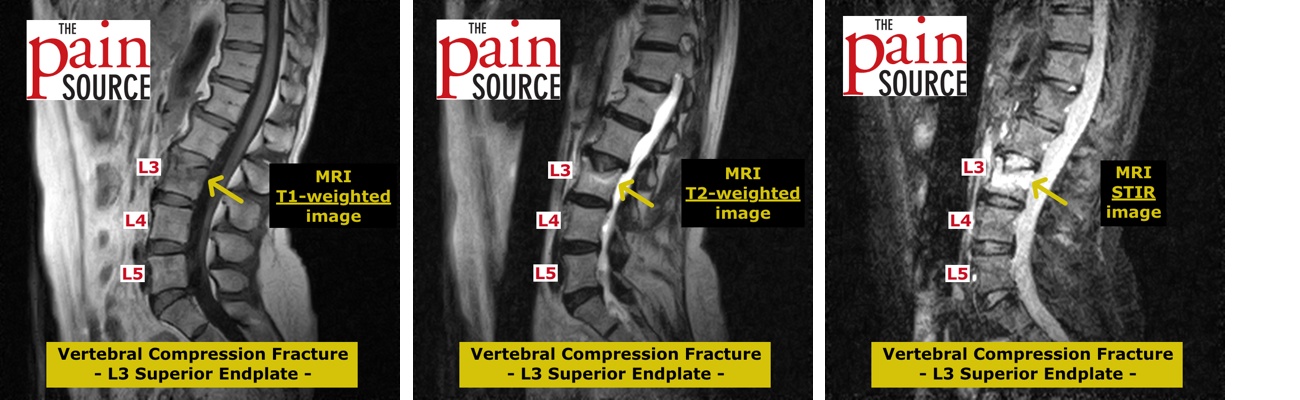

腹部のMRI MRI of the thoracic and the lumbar spine. A: sagittal T2の詳細情報

MRI of the thoracic and the lumbar spine. A: sagittal T2。116D52 | 卵巣腫瘍 国試 | テコプラ。腹部領域のMRI最新アプリケーション-技術解説 - 株式会社日立。Vertebral Compression Fracture - MRI Images - The Pain。「腹部のMRI」荒木 力定価: ¥ 13000#荒木力 #荒木_力 #本